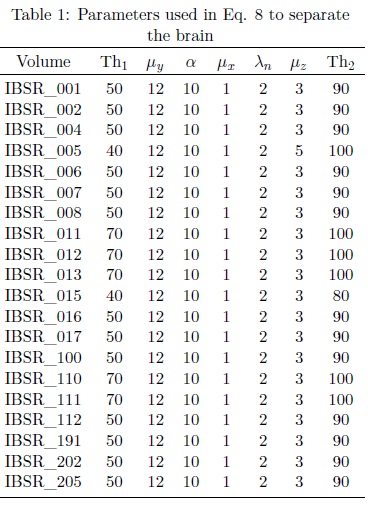

In this paper, 20 MRIs T1 (denoted as IBSR) of the head taken from the Centre for Morphometric Analysis (CMA) at the Massachusetts General Hospital (http://www.nitrc.org)[3] are processed with Eq. 8. The parameters utilized to separate the brain are shown in Table 1. From Table 1 next comments are presented:

i. The parameters λn, μz, μx, α, μy associated to Eq. 8 are similar for all segmented brains.

ii. The parameter Th1 represents a threshold used to eliminate cerebrospinal fluid with the purpose of disconnecting several regions between the brain and skull. According to the results presented in 20, the cerebrospinal fluid is eliminated with threshold values among 20-255 sections. Fig. 7 illustrates this situation. Original image is located in Fig. 7(a), whilst the threshold among 20-255 sections is presented in Fig. 7(b). Notice that, several components among the brain and the skull have been merged with the background, while the remaining regions are maintained unchanged. In Fig. 7(c) it is presented a mask between the original image (7(a)) and the image in Fig. 7(b). The image in Fig. 7(c) is convenient during the processing because when the leveling transformation reaches the regions where cerebrospinal fluid was located (dark regions); the propagation of the marker will be slower, obtaining in this way almost the separated brain with the leveling transformation.

iii. The selected size of the opening to obtain a marker is μy= 12. This value belongs to the interval 6 to 22 according to the graph in Fig. 5.

iv. The parameter λn= 2 indicates that the following filter will be applied:

with μ fixed to 3.

v. The parameter Th2 allows recovering the brain region. The threshold value is according to the information provided in [20], to eliminate dark regions.